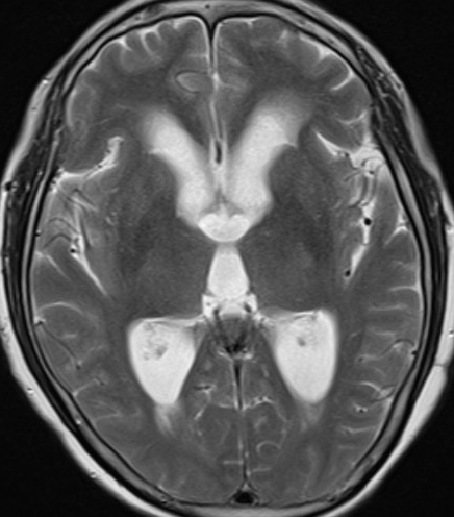

2013-5-16 MRI